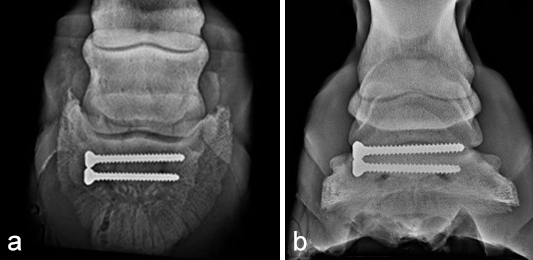

Postoperative radiographs showed accurate screw positioning (Fig 9). The horse was box-rested for 2 weeks and hand-walked for another 6 weeks. Ridden work was resumed after 2 months. The horse remained sound in the postoperative period. Four months after surgery, the radiographic definition of the cyst margins was markedly decreased.